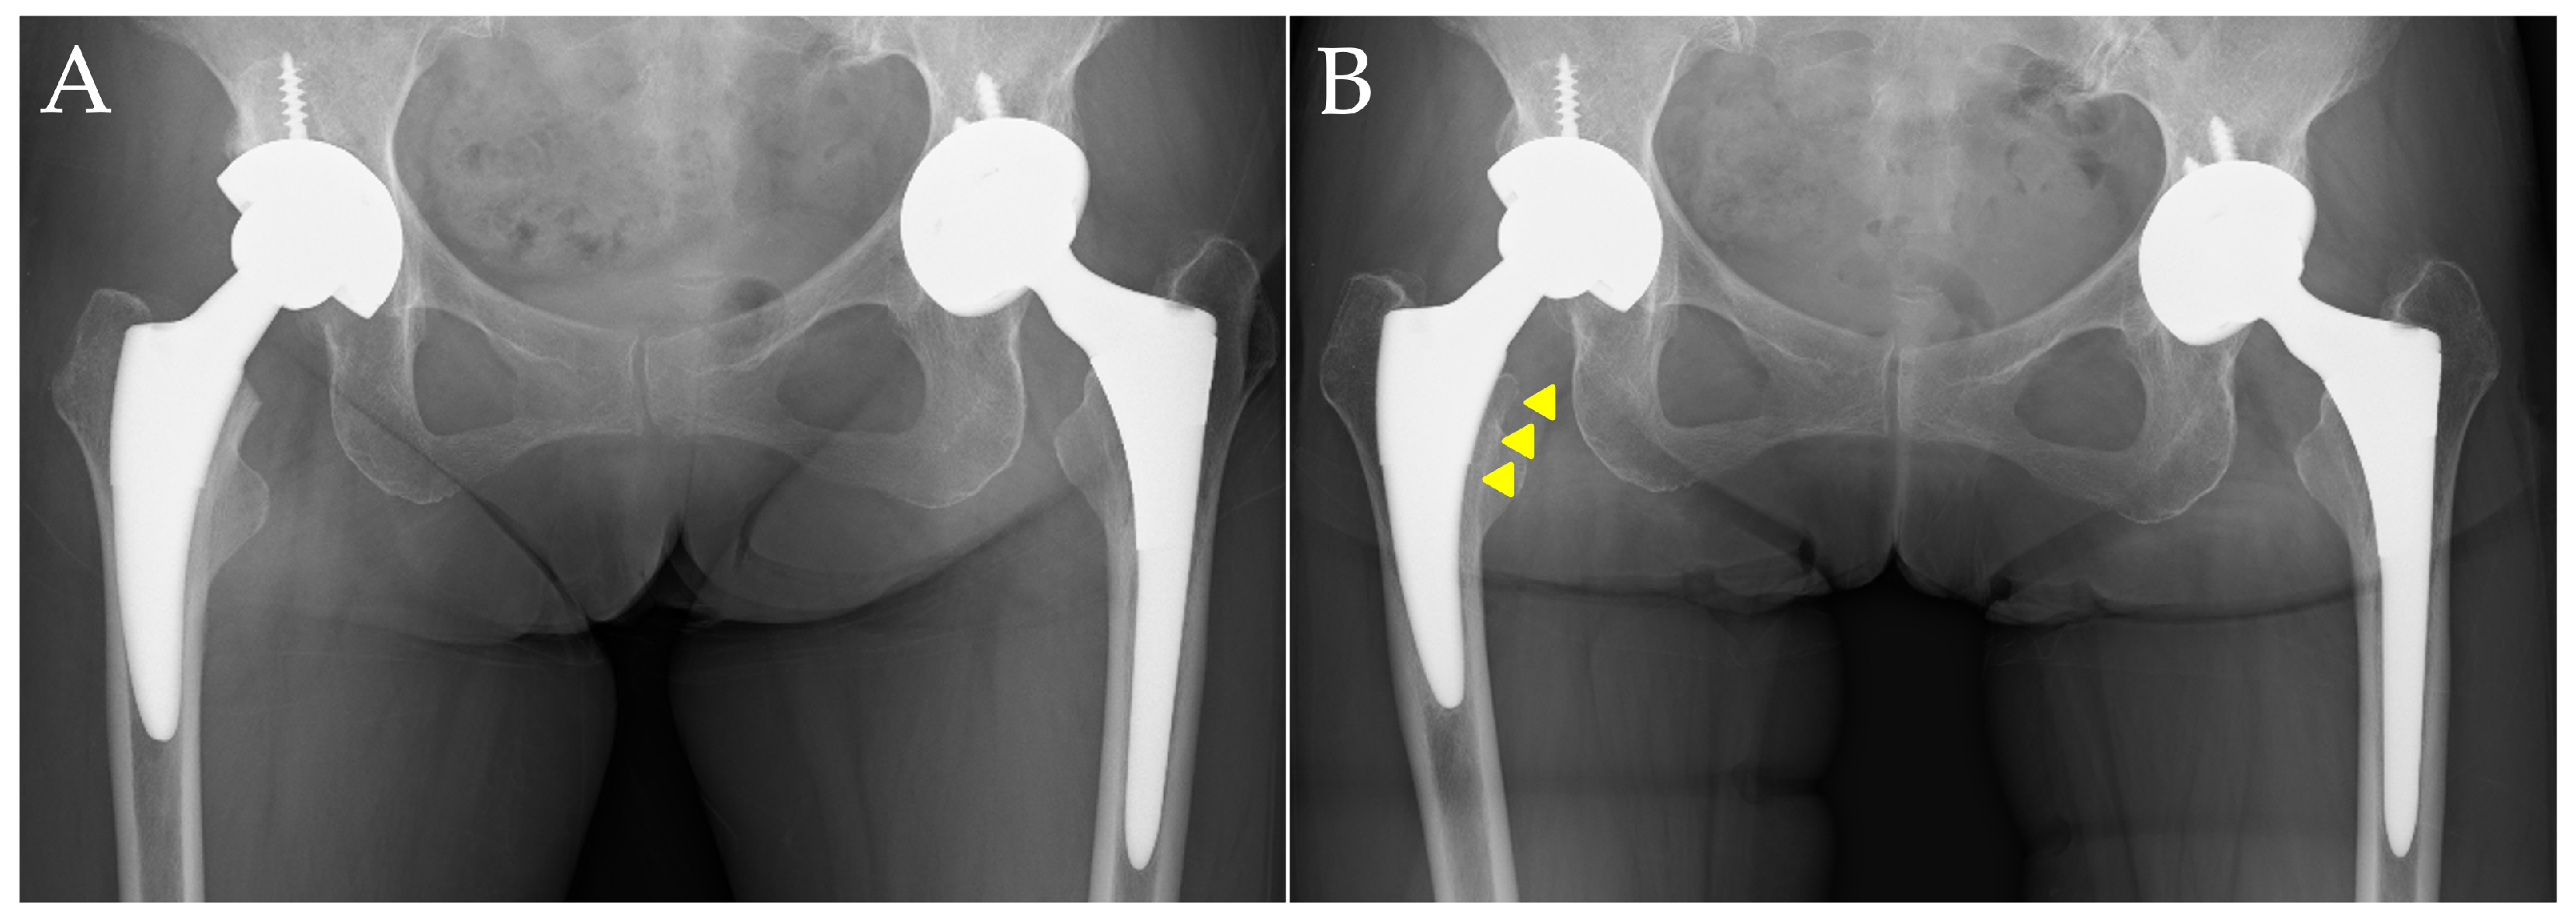

In contrast, Figure 3 presents images of a case with evidence of stress shielding, taken immediately after surgery and at one year postoperatively. This patient was a 73-year-old woman without a diagnosis or treatment for osteoporosis. The femoral stem and acetabular cup used were also the Fitmore stem and Continuum cup (Zimmer, Warsaw, IN, USA). In the images taken one year postoperatively, significant findings of proximal femoral bone atrophy were observed, with an Engh’s classification of Grade 3 (Figure 3B).

Figure 3.

A representative case of advanced stress shielding. Case of a 73-year-old female patient. (A) Anteroposterior radiograph of the hip immediately after surgery; (B) anteroposterior radiograph one year postoperatively. The arrowheads indicate cortical bone thinning due to stress shielding, with progression of thinning observed up to the midsection of the stem.